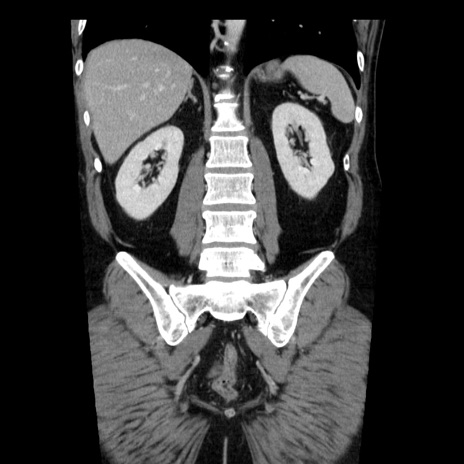

症例29(冠状断像)

【症例】40歳代男性

【現病歴】2日前から胃痛あり。徐々に周期的な激痛に変化した。本日になっても激痛があるため受診。

【身体所見】意識清明、BT 38-39℃台あり、腹部:膨満、やや硬、右下腹部に圧痛あり。

【データ】WBC 8500、CRP 23.26